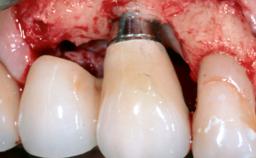

This case describes both a surgical and an anti-infective approach for the management of peri-implantitis, including treatment of the entire dentition to eliminate any deep periodontal pockets that could serve as reservoirs for bacterial re-colonization at the implant site. A 65-year-old female patient was referred to the periodontist in 2013 for assessment and management of an infection at implant 12. On examination, probing depths at implant 12 were 11 mm with suppuration and bleeding on probing.